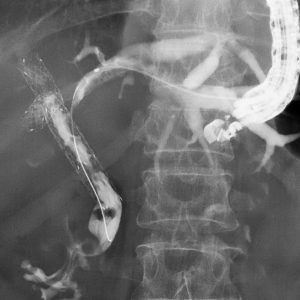

- 術後再建腸管に対する DB-ERCP検査

重症急性膵炎後のWONに対するEUS下膿瘍ドレナージ

肝門部胆管癌に対するEUS下胆道ドレナージ

急性胆嚢炎に対するEUS下胆嚢ドレナージ(LAMS留置)